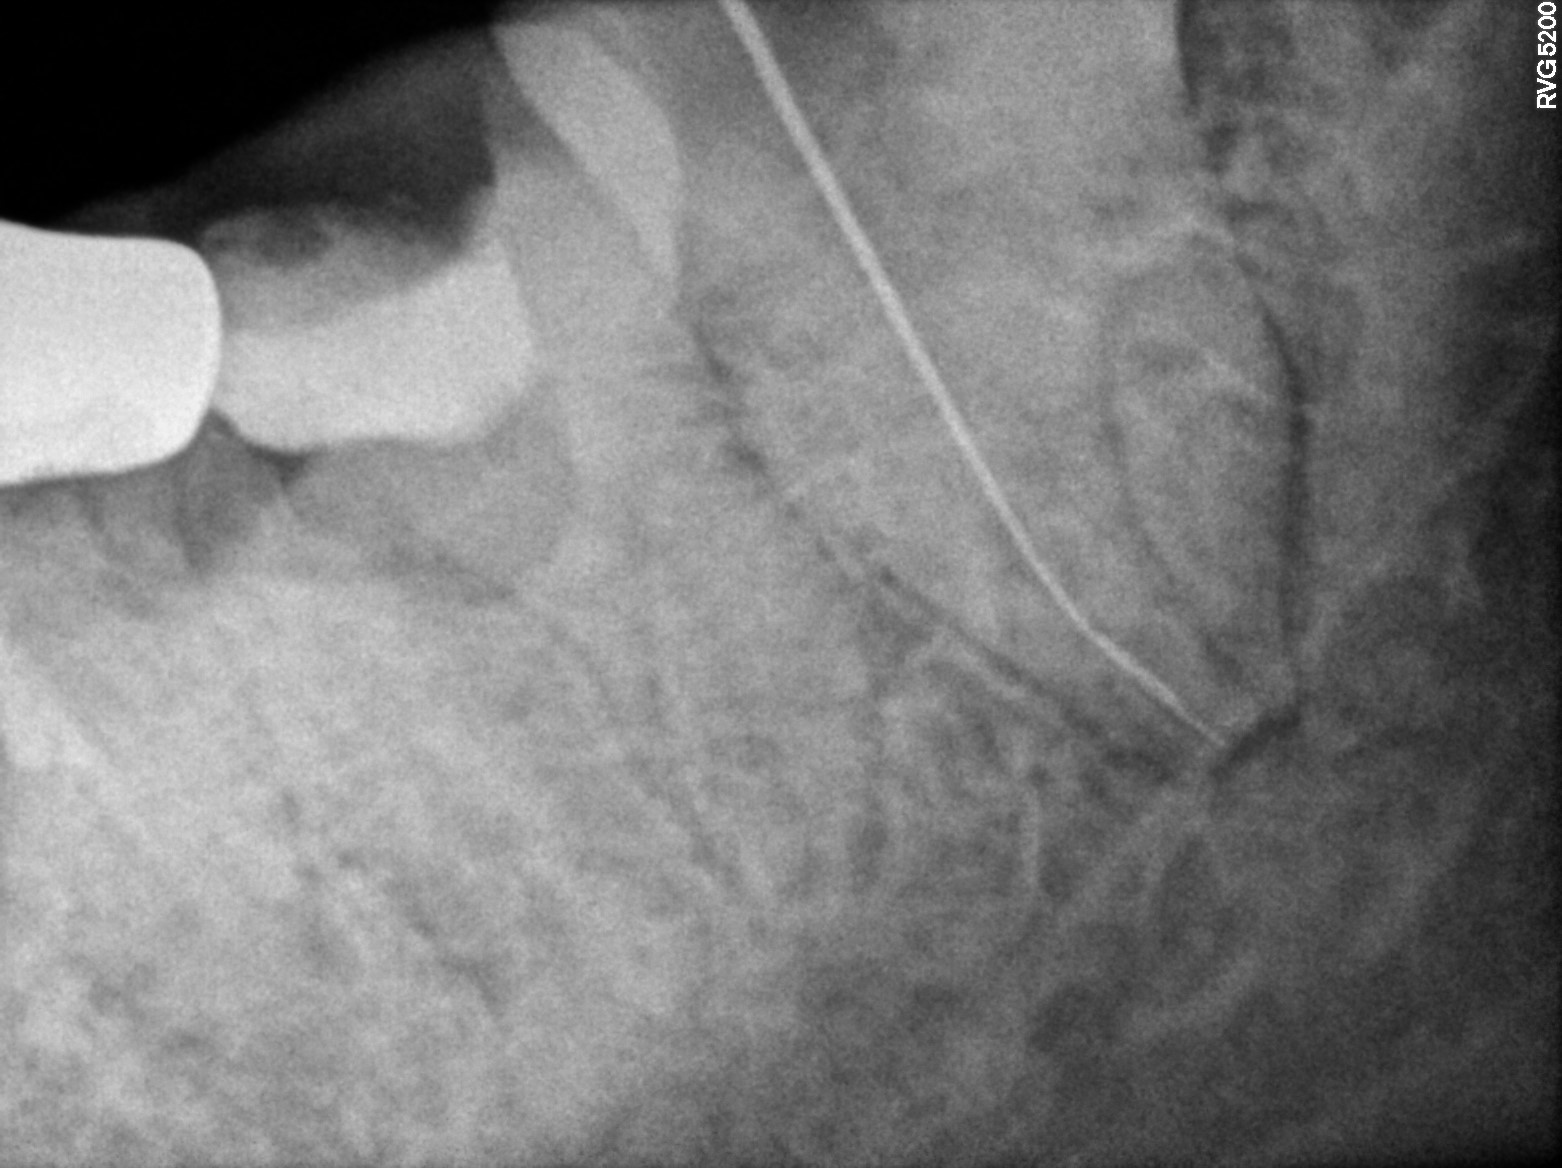

Dental Radiographs FHIR: DocumentReference · LOINC 24641-7

R38.jpg

24641-7